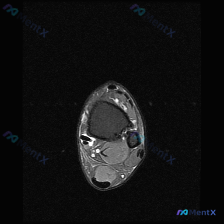

刚看到一份踝关节MRI单张图像的分析资料,整理了完整的读片思路给大家参考。 影像基本信息 这是一张踝关节轴位MRI,从信号特征判断属于T2或压脂序列(水呈高信号),核心发现是: 1. 距骨骨皮质形态完整,未见明确骨折线,但骨髓腔内信号有异常改变 2. 关节周围可见广泛弥漫性高信号,明确提示软组织液体...

今天看到一个很有讨论价值的读片病例,整理一下信息和分析思路给大家参考。 病例基本信息 问题:患者主诉踝关节感觉有软组织积液,请读片判断 影像:踝关节MRI-脂肪抑制序列-轴位单张图像 影像详细评估 这是踝关节远端水平的轴位扫描,先给大家整理一下观察结果: 1. 骨骼:胫骨远端、腓骨远端骨髓信号正常,...

看到一份只有踝关节MRI影像的病例,这里给大家整理一下读片思路和容易踩的坑,一起来讨论下。 病例核心信息: 这是踝关节MRI-T2序列轴位图像,主要的异常发现如下: 1. 解剖结构基本正常:跟腱、腓骨长短肌腱、内踝后方各肌腱走行连续,信号都正常;距骨、跟骨骨髓信号没有异常水肿或破坏,没有骨折或明显韧...

拿到这张踝关节MRI T2轴位片,问题问软组织液有什么表现,整理一下病例信息和分析思路给大家参考: 基本影像信息 这是踝关节MRI T2序列轴位图像,核心发现是: 1. 骨骼:距骨等主要骨性结构轮廓连续,无明显骨皮质中断,骨髓无大范围明显T2高信号水肿 2. 肌腱韧带:外侧腓骨长短肌腱走行区可见不规...